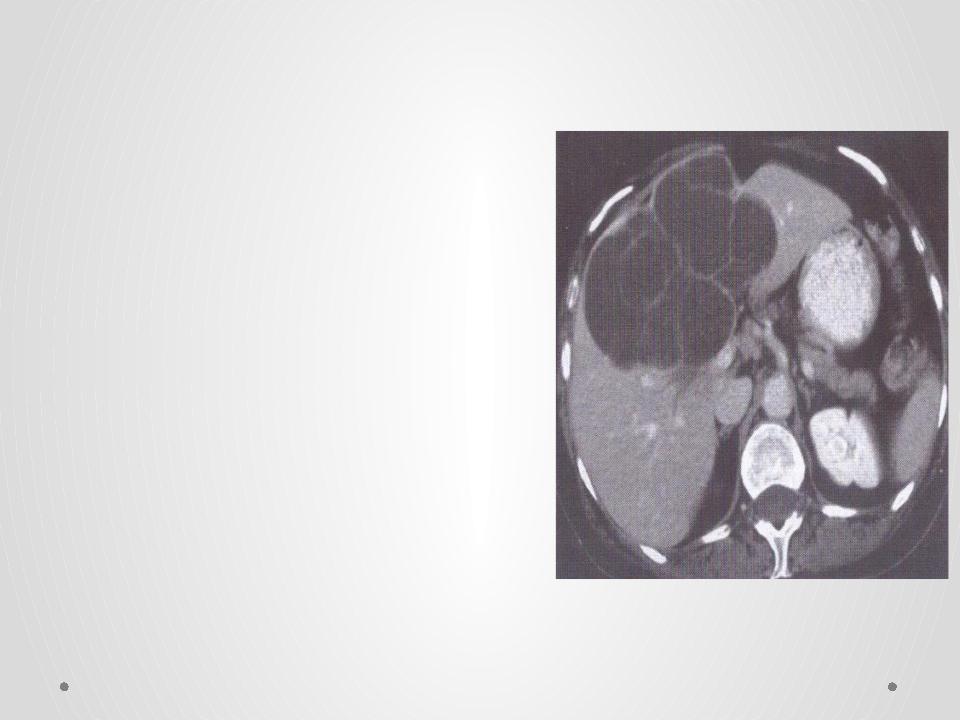

В процессе гинекологического УЗИ точно устанавливаются размеры кистомы, толщина капсулы, уточняется наличие камер и сосочковидных разрастаний. При пальпации живота, а также с помощью УЗИ брюшной полости может выявляться асцит. Обнаружение опухоли яичника требует исследования онкомаркера СА-125. В ряде случаев для уточнения диагноза целесообразно проведение КТ или МРТ малого таза. Окончательное подтверждение диагноза и выяснение морфологической формы папиллярной кистомы яичника производится в процессе диагностической лапароскопии, интраоперационного гистологического исследования.

Довольно информативным (но и более дорогостоящим) является компьютерная томография (КТ) или магнитно-резонансная томография (МРТ). Эти методики позволяют уточнить расположение кисты, размеры, структуру, контуры, содержимое, взаимоотношение с предлежащими органами, выявить признаки злокачественного роста.

С помощью магнитно-резонансной томографии органов малого таза с контрастированием уточняют расположение, размер и структуру кисты.